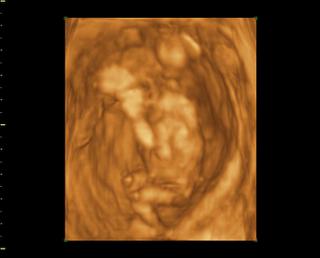

Tak čaute kočky, som doma z 3Dčka, dnes som 14+1 mám plno krásnych fotiek na kľúči, najbližšie mám prísť na 3Dčko v 20tt a potom tretí krát okolo 25 tt a vtedy dostanem aj DVDčko zo všetkých troch UV. Ale fotky aj videá nám dal na USB kľúč takže už teraz mám všetky 🙂 Čo sa pohlavia týka, tak to vyzerá na chlapca, ešte mám aj jednu fotku kde to zreteľne vidieť že to bude asi chlapec. bábo bolo aktívne strašne veľa skákalo a pohybovalo sa, stále si rúčkami chytalo hlavičku (to robí aj Danko stále 😀 ) Priateľ bol vnútri so mnou takže to celé videl.